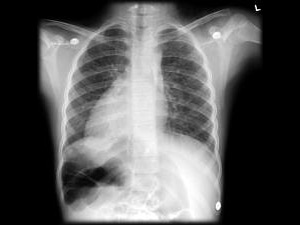

வலது பக்கத்தில் இதயம் இருந்தாலும் ஆபத்தில்லை

இதயமானது மனிதனுக்கு இடது பக்கம்தான் இருக்கும். இதுதான் படைப்பு. ஆனால் சென்னையைச் சேர்ந்த இந்திரா என்ற பெண்ணுக்கு வலது பக்கம் இதயம் இருப்பது பெரும் ஆச்சரியத்தை ஏற்படுத்தி உள்ளது. இவருக்கு வலதுபுறம் இருக்க வேண்டிய கல்லீரல் குடல் போன்ற பாகங்கள் இடதுபக்கமாகவும், இடதுபுறம் இருக்கவேண்டிய உறுப்புகள் வலது புறமாகவும் மாறி இருக்கிறது.

கடந்த 6 மாதமாக இந்திராவுக்கு அடிக்கடி நெஞ்சுவலி, மயக்கம், சோர்வு ஏற்பட்டது. கடந்த 25-ந்தேதி சென்னை அரசு ஆஸ்பத்திரியில் இருதய நோய் சிகிச்சை பிரிவில் சேர்த்தனர். அங்கு ஸ்கேன் பரிசோதனை செய்தபோது இடது பக்கம் இருக்க வேண்டிய இதயம் உள்ளிட்ட பாகங்கள் வலது பக்கத்திலும், வலது பக்கம் இருக்க வேண்டிய கல்லீரல், குடல் உள்ளிட்ட பாகங்கள் இடது பக்கத்திலும் இருப்பது கண்டறியப்பட்டது. இதனால் அவரது உயிருக்கு ஆபத்து இல்லை என்றாலும் இதயத்தில் அடைப்பு ஏற்பட்டு இருப்பதால் அறுவை சிகிச்சை செய்யப்பட்டு பின்னர் பேஸ் மேக்கர் கருவி பொருத்தப்பட்டது.

கோடியில் ஒருவருக்கு இதேபோல் வலது பக்கத்தில் உறுப்புகள் மாறி இருக்கும் இதனால் உயிருக்கு ஆபத்து எதுவும் ஏற்படாது என மருத்துவர்கள் தெரிவித்துள்ளனர்.